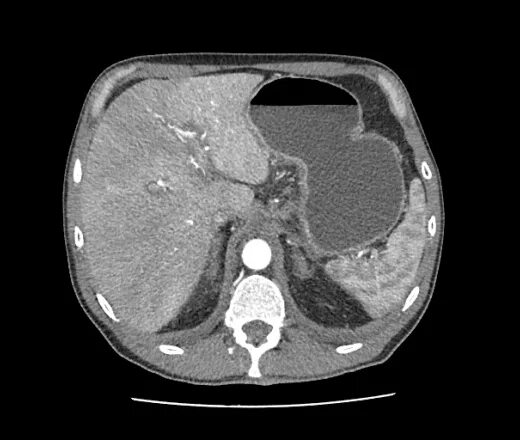

Язва желудка кт